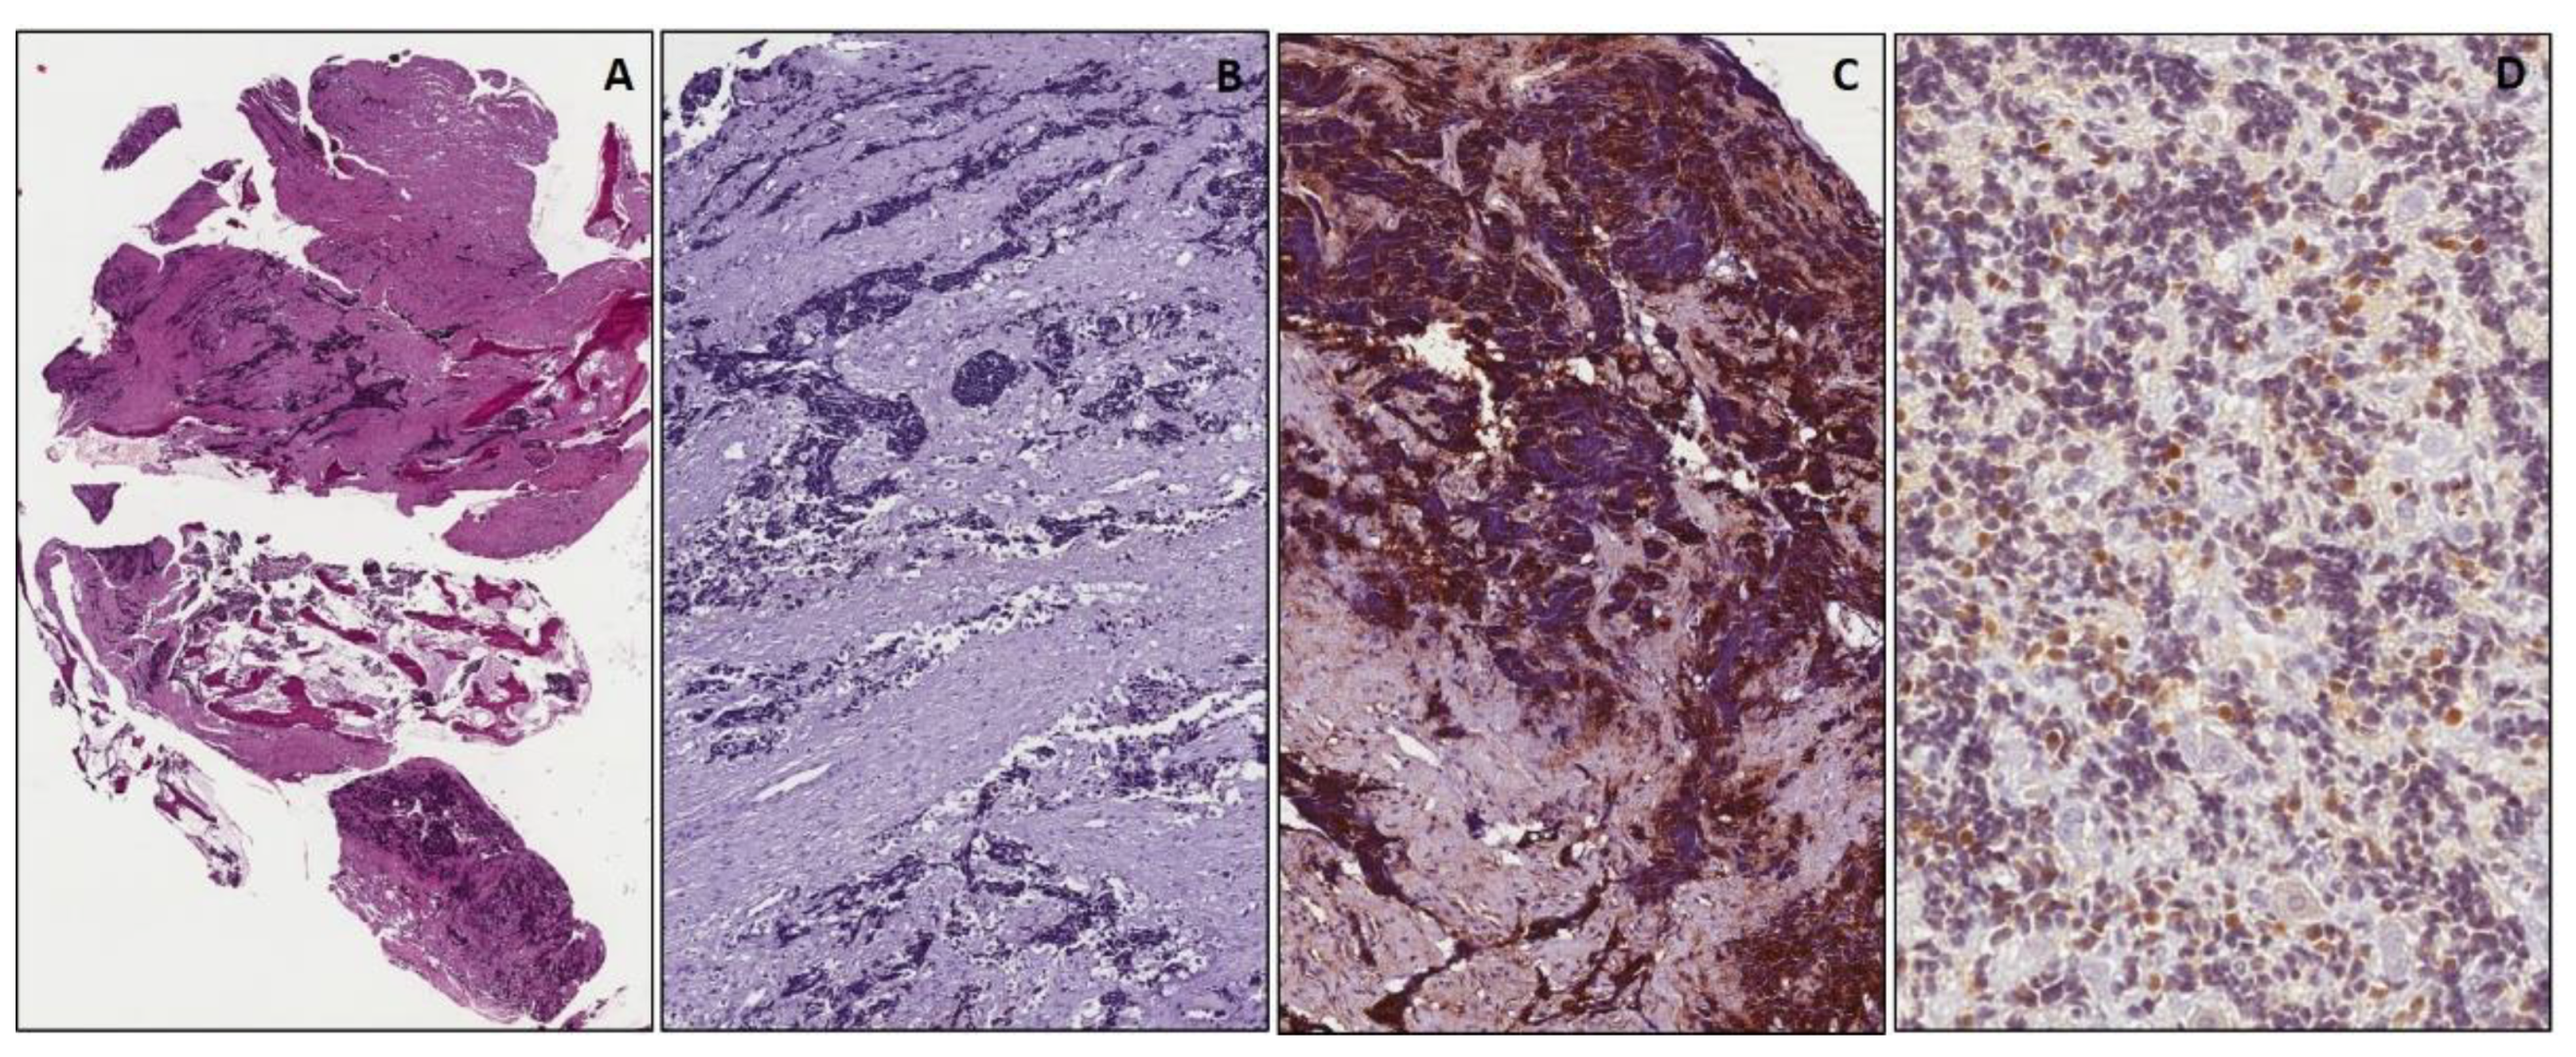

WT1 and Cyclin D1 Immunohistochemistry: A Useful Adjunct for Diagnosis of Pediatric Small Round Blue Cell Tumors on Small Biopsies

| Tumors | WT1 | Cyclin D1 | Desmin | Myogenin | MyoD1 | CD99 | NB84 | CD56 | TdT |

|---|---|---|---|---|---|---|---|---|---|

| RMS (33 cases) | 33/33 | 0/33 | 33/33 (*) | 33/33 (*) | 28/33 | 0/33 | 0/33 | 3/33 | 0/33 |

| EWS (14 cases) | 0/14 | 14/14 | 0/14 | 0/14 | 0/14 | 14/14 (**) | 0/14 | 0/14 | 0/14 |

| NB (44 cases) | 0/44 | 44/44 | 0/44 | 0/44 | 0/44 | 0/44 | 43/44 (***) | 44/44 | 0/44 |

| WT (3 cases) | 3/3 | 0/3 | 0/3 | 0/3 | 0/3 | 0/3 | 0/3 | 3/3 | 0/3 |

| LL (11 cases) | 0/11 | 0/11 | 0/11 | 0/11 | 0/11 | 7/11 | 0/11 | 0/11 | 11/11 |